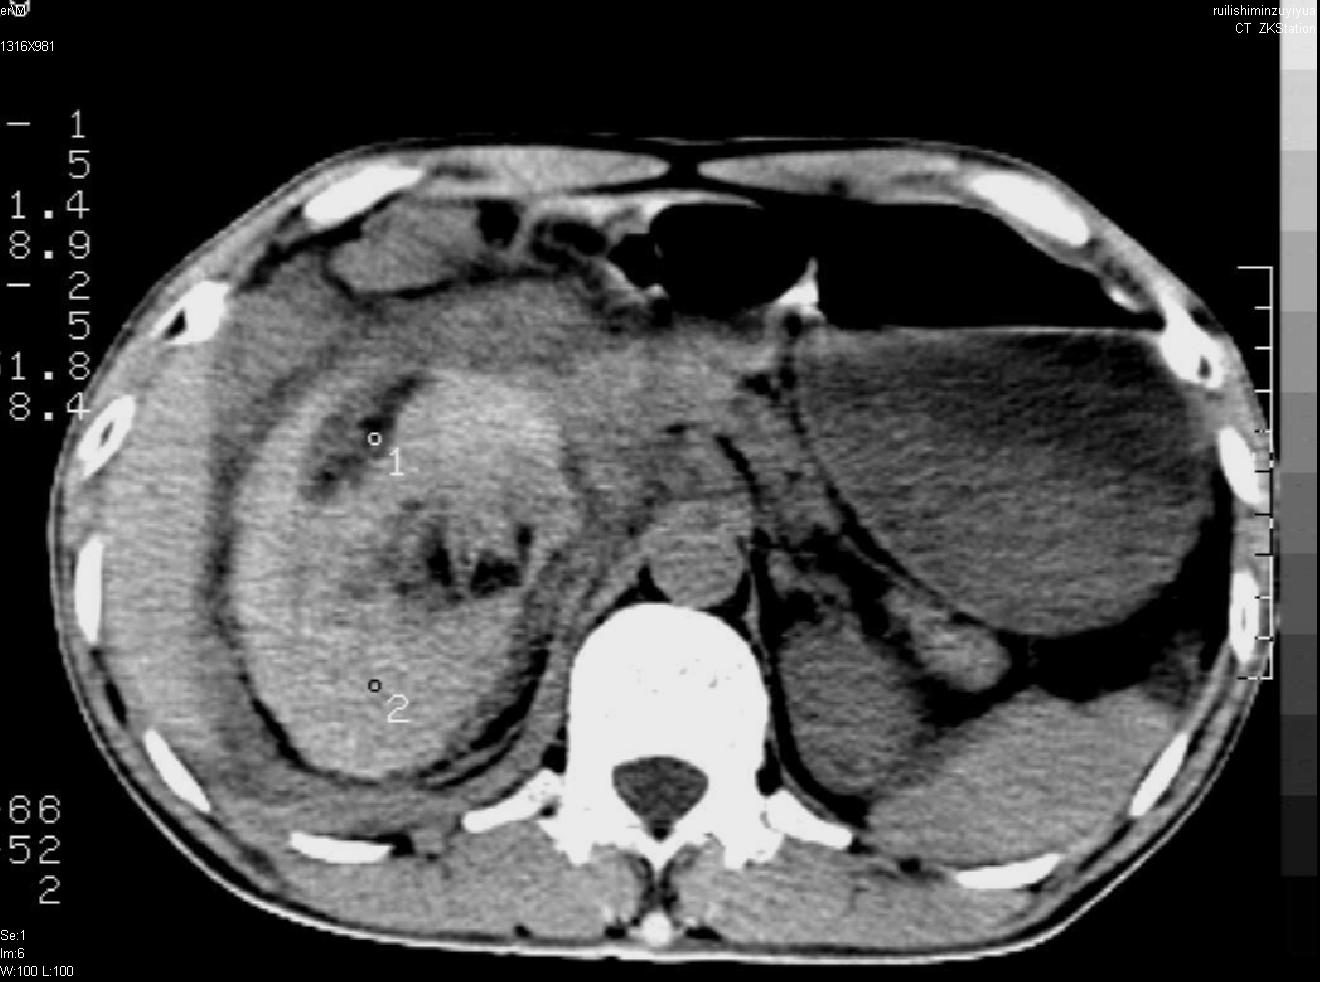

以下是引用liuyue在2007-12-3 6:27:00的发言:[br]右肾区可见密度不均匀、边缘欠清之肿块影,肾脏筋膜增厚,周围脂肪密度增高。右侧胸膜腔内可见少量液体密度影。考虑:1.右肾错构瘤(肾血管平滑肌脂肪瘤)可能性大。2.右侧少量胸腔积液。[br] 鉴别:1.肾脂肪肉瘤。2.肾平滑肌肉瘤。3.肾错构瘤恶变。